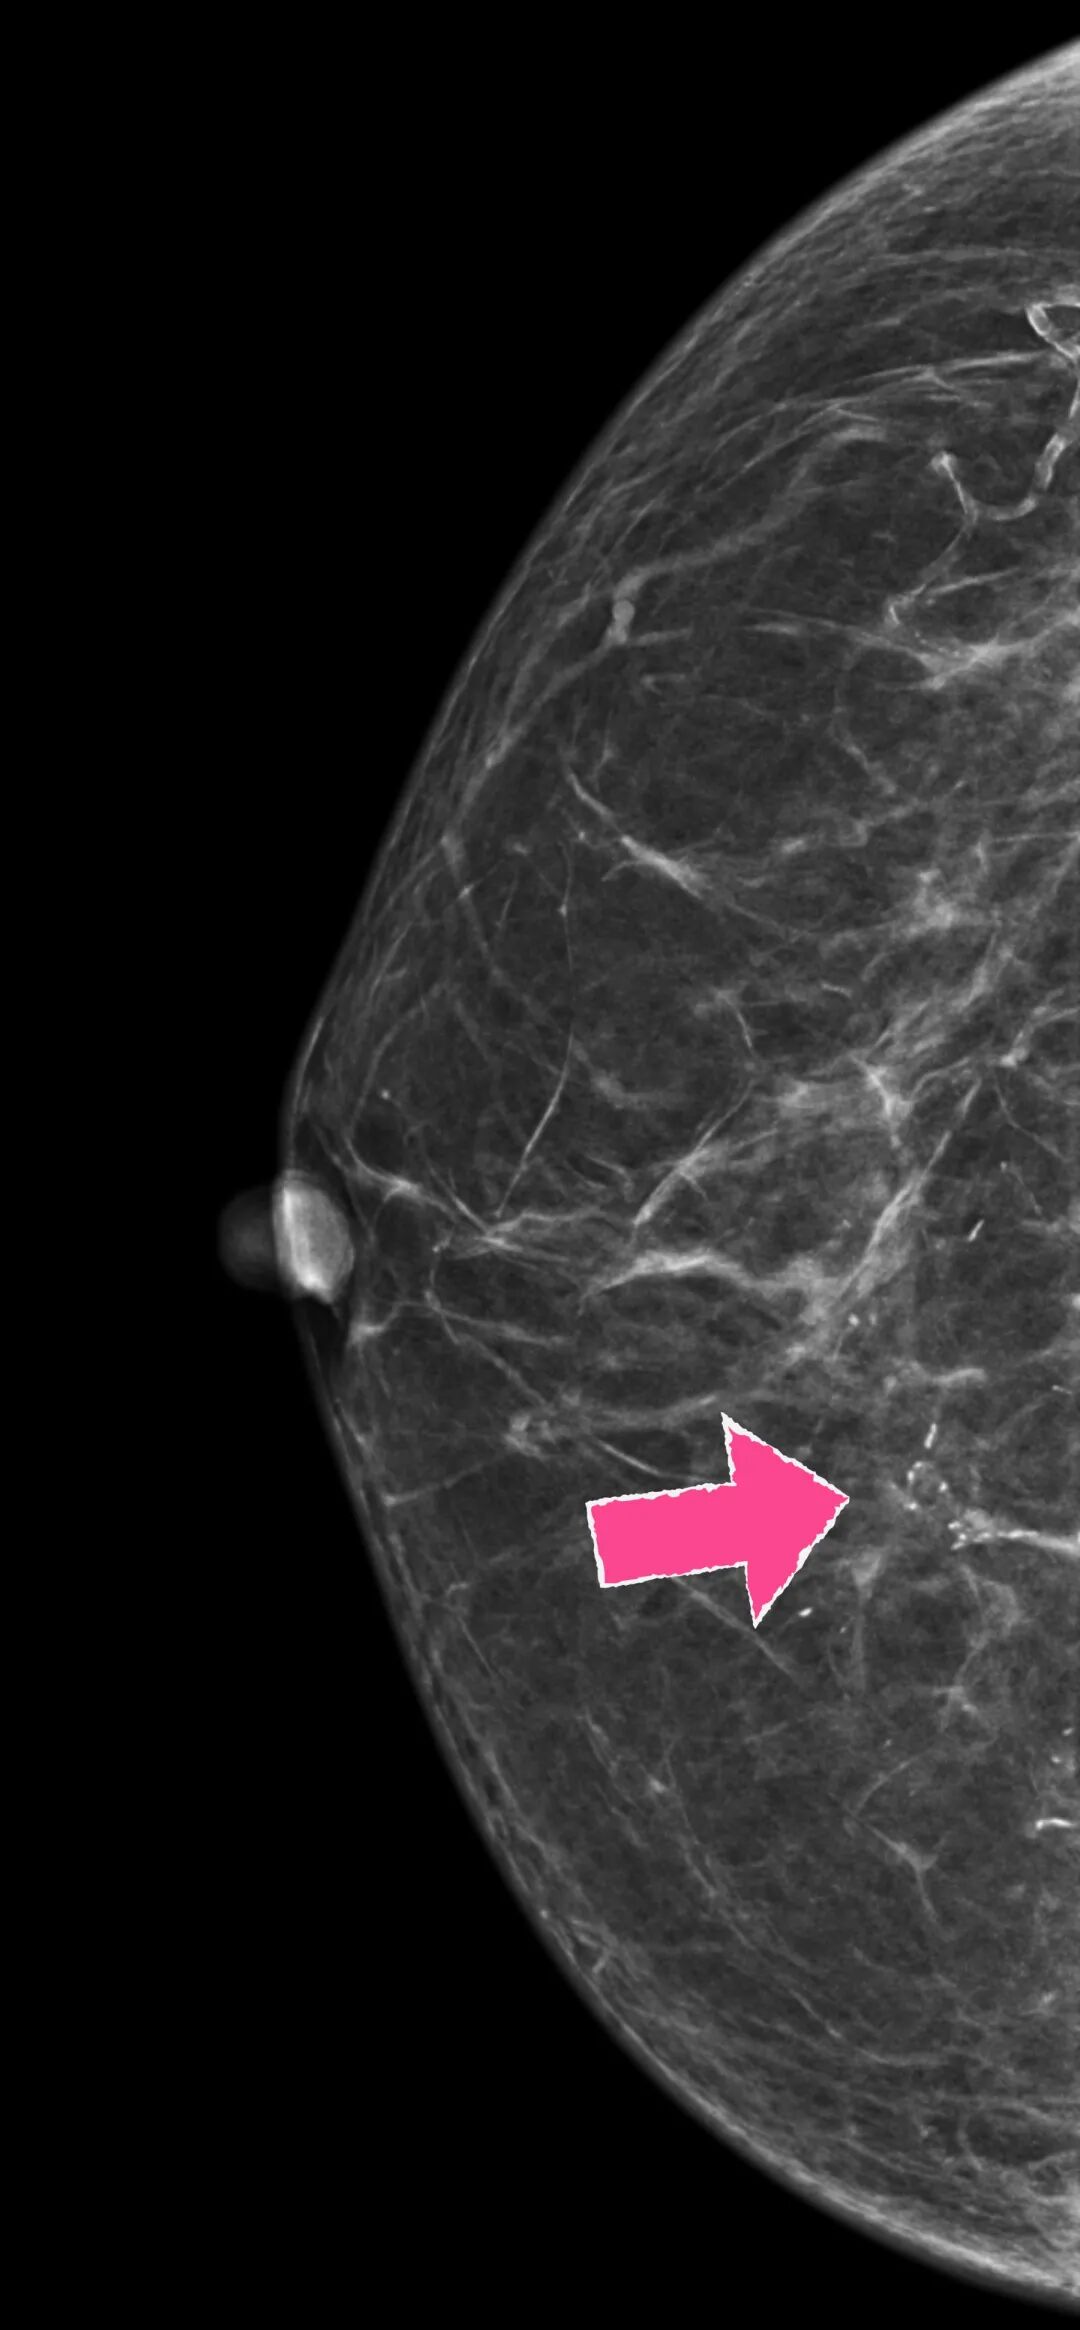

实际上,真正需要警惕的乳腺病变,除了那些“长的叛逆”的肿块,还有一些早期高风险的病灶,有的仅仅表现为乳腺钼靶上不起眼的“成簇小芝麻点状”的或者不定形钙化灶。

这类病灶哪怕个头再小,再不起眼,也得想办法“取”出来“查明身份”。

比如这种👇

▲某患者体检发现右乳钙化灶,放射科提示可疑恶性钙化(“小白点”)

但在大部分手术中,这小钙化灶在B超上是看不到的,开刀时更是看不见摸不着,给乳腺癌早期筛查带来极大障碍。